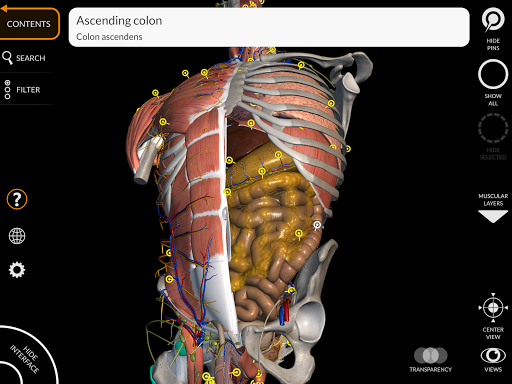

"Anatomía - Atlas 3D" permite estudiar la anatomía humana de forma fácil e interactiva.

A través de una interfaz sencilla e intuitiva es posible observar cada estructura anatómica desde cualquier ángulo.

Los modelos anatómicos 3D son especialmente detallados y con texturas de hasta una resolución de 4k.

La subdivisión por regiones y las vistas predefinidas facilitan la observación y el estudio de partes individuales o grupos de sistemas y las relaciones entre los diferentes órganos.

nervioso • Sistema respiratorio • Sistema digestivo • Sistema urogenital (masculino y femenino) • Sistema endocrino • Sistema linfático • Sistema ocular y auditivo CARACTERÍSTICAS • Interfaz sencilla e intuitiva • Rotar y hacer zoom en cada modelo en el espacio 3D • Opción para ocultar o aislar uno o varios modelos seleccionados • Filtro para ocultar o mostrar cada sistema • Función de búsqueda para encontrar fácilmente cada parte anatómica • Función de marcador para guardar vistas personalizadas • Rotación inteligente que mueve el centro de rotación automáticamente • Función de transparencia • Visualización de músculos a través de niveles de capas desde las superficiales hasta las más profundas • Al seleccionar un modelo o un pin, aparece el término anatómico relacionado • Descripción de los músculos: origen, inserción, inervación y acción • Mostrar/ocultar interfaz de usuario (muy útil con pantallas pequeñas) MULTILINGÜE • Los términos anatómicos y la interfaz de usuario están disponibles en 11 idiomas: latín, inglés, francés, alemán, italiano, portugués, turco, ruso, español, Chino, japonés y coreano • Los términos anatómicos se pueden mostrar en dos idiomas simultáneamente REQUISITOS DEL SISTEMA • Android 8.0 o posterior, dispositivos con al menos 3 GB de RAM Reversi

• Sistema digestivo